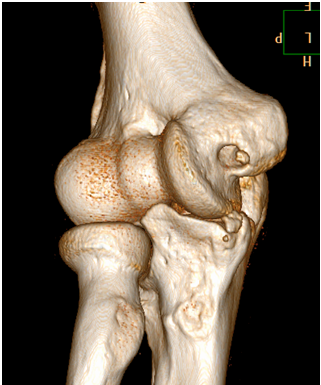

Computed Tomography

Last year we performed nearly 2,500 adult non-emergent MSK CT examinations at our Memorial and University Campuses of UMMMC and Marlborough Hospital. In addition to routine diagnostic CT exams, we also perform specialty MSK studies using CT, including:

- CT arthrograms (Marlborough Hospital and Memorial Campus)

- CT guided soft tissue and bone tumors of the extremities (University Campus)